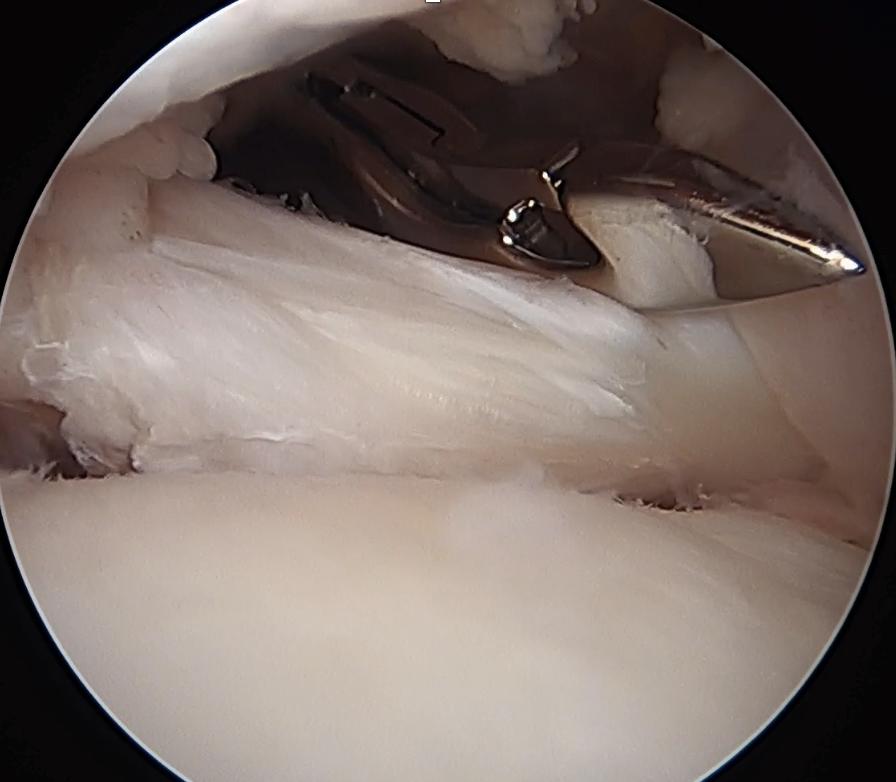

Suture passage through anterior portal or anterolateral portal and tie sutures through anterior portal